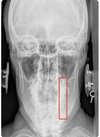

APOM ANATOMICAL LANDMARKS

maxillary sinus

29

frontal sinus

30

nasal aperature

31

nasal spine + septum

32

lower teeth

33

upper teeth

34

mandible

35

jugular process

36

A-P open mouth

rim of foramen magnum

37

anterior arch c1

38

posterior arch c1

39

A to P open mouth

lateral mass of c1

40

transverse process c1

41

medial inferior tip of occipital condyles

42

mastoid air cells

43

A-P open mouth view

pedicle shadow c2

44

spinous process c2